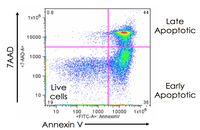

- Evaluation of cell apoptosis by flow cytometry

- Examination of living and dead cells